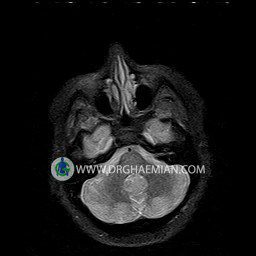

پزشکان اغلب از تصویربرداری ام آر آی برای تشخیص و درمان عارضه های پزشکی که فقط با استفاده از اشعه ایکس یا میدان مغناطیسی و امواج رادیویی قابل مشاهده است، استفاده می کنند. دستگاه ام آر آی تصاویر دقیق از ساختار های داخلی بدن ایجاد می کند. در این کیس نوریت اوربیت چب و سلای خالی بیمار مشاهده می شود.

ORBIT MRI

(with and without contrast)

Technique:Axial T1 , Axial , sagittal , coronal FSE T2 , coronal T1, sagittal fat sat T2 , Axial , sagittal T1 post Gd .

REPORT :

The both orbit are symmetrical and of normal size , with normal development of the orbital cones .

The bony orbital walls show a normal configuration with smooth and, sharp margins .

No foci of bone destruction , no circumscribed expansion of the bony or soft – tissue components of the orbital are evident .

The globes are symmetrical and of normal size and the ocular contents show normal signal characteristics .

The ocular walls are smooth , sharply defined , and of normal thickness .

The retrobulbar fat, ophthalmic vein and lacrimal apparatus are unremarkable .

Evaluable portions of the neurocranium and paranasal sinuses show no abnormalities .

No seen any evidence of ocular herniation

– Small fluid around the left optic nerve with mild edema suggestive for left optic neuritis

– Extension of suprasella cistern to sella with thin pituitary gland in floor of sella ( empty sella )

are seen

REPORTED BY :Dr DrNaser. Ghaemian.